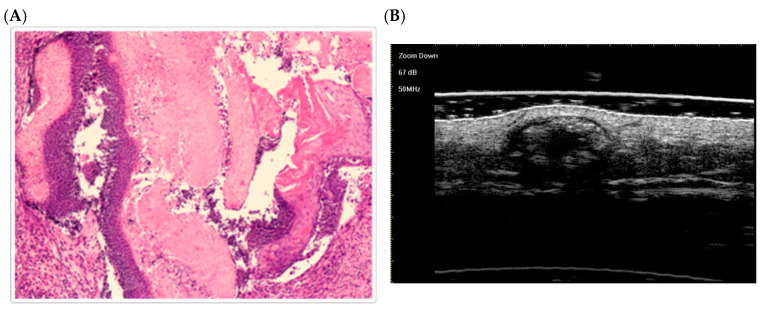

毛囊基质瘤是起源于毛囊基质细胞的良性肿瘤,是儿科患者中最常见的皮肤肿瘤。毛瘤基质瘤可能与遗传综合征有关,如肌强直性营养不良症、家族性腺瘤性息肉病(FAP)、特纳综合征、Rubinstein-Taybi综合征、Kabuki综合征和Sotos综合征。本研究回顾了在综合征背景下发生的毛囊基质瘤的文献,并提出了一个与Apert综合征相关的新病例。使用PubMed和Cochrane数据库进行系统综述,重点关注病例报告、病例系列和描述与综合征相关的毛瘤基质瘤的综述。最初共筛选了1272篇文章;在去除重复和排除无综合征诊断或缺乏足够数据的文章后,我们回顾了81篇全文文章。总的来说,96例与遗传综合征相关的毛囊基质瘤被确定。文献中没有关于Apert综合征患者不发展为毛瘤基质瘤的报道。毛囊间质瘤主要影响儿科患者,有轻微的女性优势,往往是潜在的遗传综合征的第一表现。我们的研究强调了以前未报道的毛瘤基质瘤与Apert综合征的关联,提供了分子见解。本研究有助于了解毛囊基质瘤在综合征背景下的临床和分子特征,并强调了基因分析对准确诊断和管理的重要性。

Pilomatricomas are benign tumors originating from hair follicle matrix cells and represent the most common skin tumors in pediatric patients. Pilomatricomas may be associated with genetic syndromes such as myotonic dystrophy, familial adenomatous polyposis (FAP), Turner syndrome, Rubinstein-Taybi syndrome, Kabuki syndrome, and Sotos syndrome. This study reviews the literature on pilomatricomas occurring in syndromic contexts and presents a novel case linked to Apert syndrome. A systematic review was conducted using PubMed and Cochrane databases, focusing on case reports, case series, and reviews describing pilomatricomas associated with syndromes. A total of 1272 articles were initially screened; after removing duplicates and excluding articles without syndromic diagnoses or lacking sufficient data, 81 full-text articles were reviewed. Overall, 96 cases of pilomatricomas associated with genetic syndromes were identified. Reports of patients with Apert syndrome who do not develop pilomatricomas are absent in the literature. Pilomatricomas predominantly affect pediatric patients, with a slight female predominance, and are often the first manifestation of underlying genetic syndromes. Our study highlights previously unreported associations of pilomatricoma with Apert syndrome, providing molecular insights. This study contributes to understanding the clinical and molecular features of pilomatricomas in syndromic contexts and underscores the importance of genetic analysis for accurate diagnosis and management.